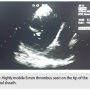

After advancing the spiral catheter inside the first transseptal sheath, a mobile thrombus was visualized under ICE in the left atrium (Figure 1). Upon further review of these images, it was found that the thrombus was attached to the distal end of the sheath where the spiral catheter was protruding.